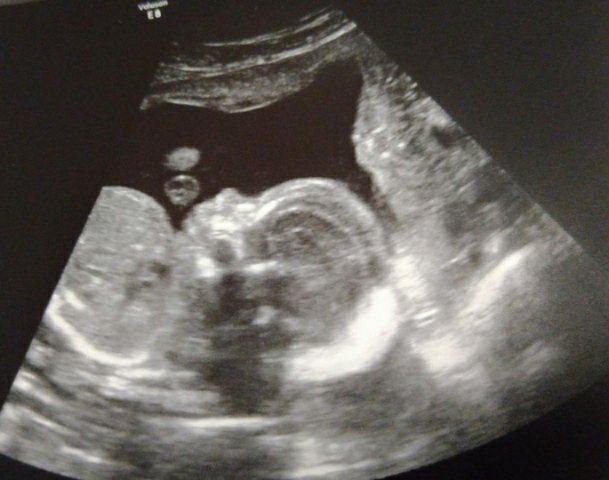

27+4